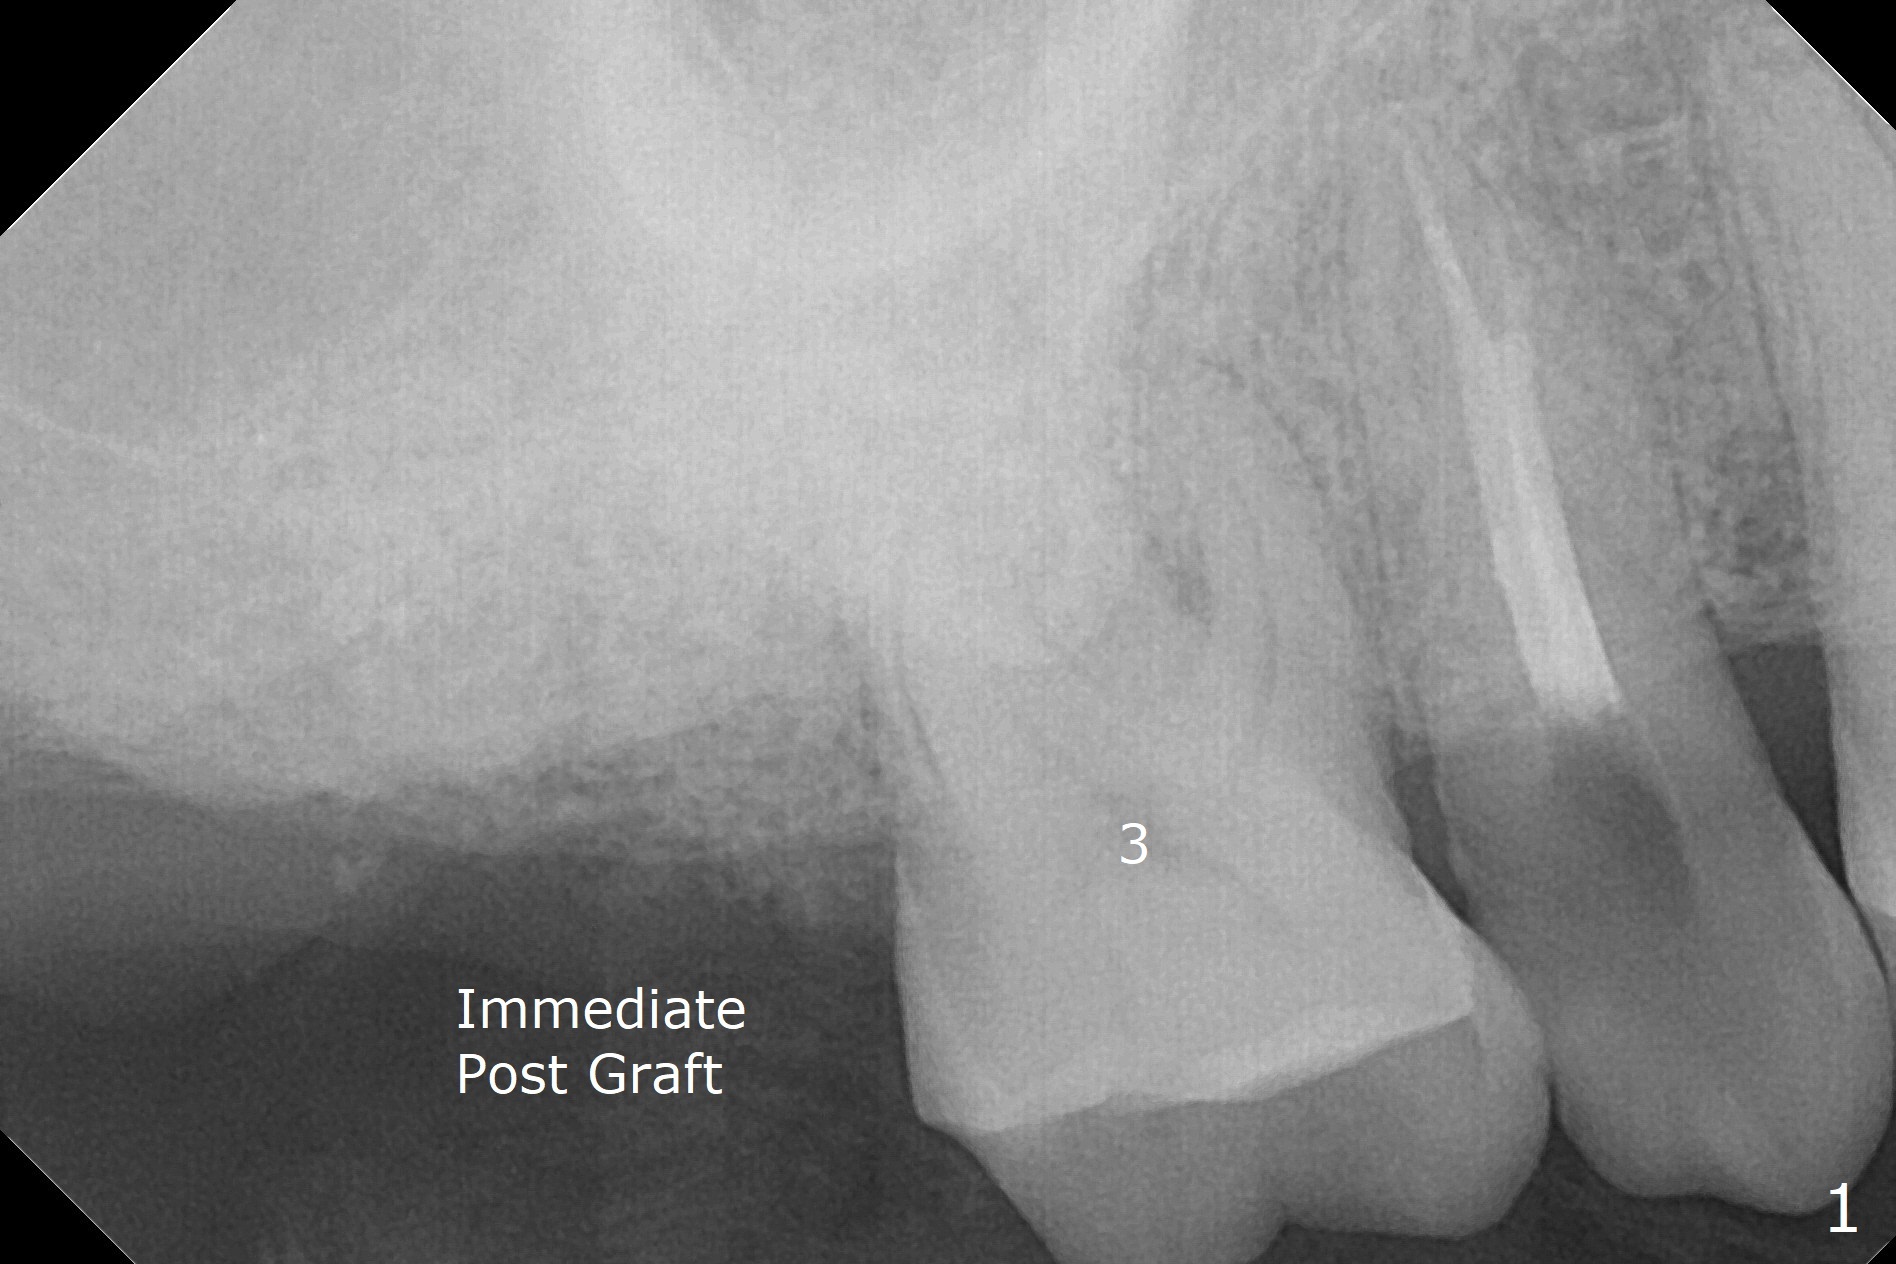

The apices of the mesio-buccal (MB) and disto-buccal (DB) roots are soft when the tooth #2 is extracted. After socket debridement, there is no air leak. Minera-lized cortical and cancellous mix (50/50) hydrated with ~ .25 ml of .3 mg/ml of rhPDGF-BB is placed in MB and DB sockets and pushed upward with a curette. Finally the whole socket is filled up to the crest and a piece of 8x8 mm BioXclude is placed and sutured in placed with 4-0 PGA (Fig.1-3). In fact sinus lift is accomplished moderately MB and DB (Fig.2,3). In fact the density of the bone graft 6 months postop remains the same as immediate postop, similar to the native bone as well (Fig.4,5). With socket preservation, a longer implant will be placed at #2 (Fig.6, as compared 8.5 mm at #15 without bone graft).